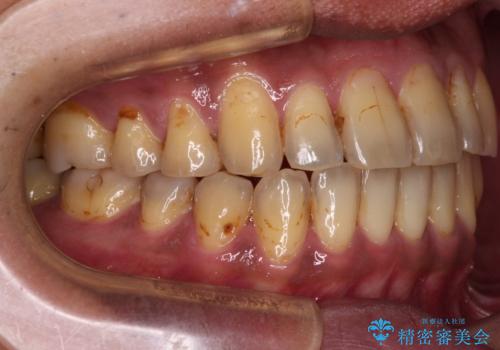

前歯のクロスバイトを改善 ワイヤー装置での非抜歯矯正

- 骨格的な咬み合わせのズレ、前歯のデコボコとクロスバイトを気にして来院された患者様です。

骨格のズレが顕著であると診断され、マウスピース矯正では奥歯の咬み合わせが整えにくいと判断し、ワイヤー装置による矯正治療を行うこととしました。

上下の叢生は速やかに改善できましたが、右側のクロスバイトの改善に1年以上の期間を要しました。